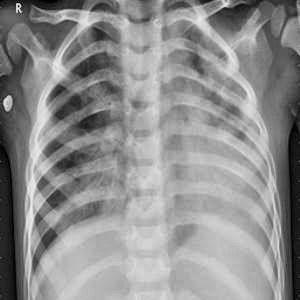

Yuklangan rasm

Tashxis natijasi

Bemor: Pnevmoniya kasalligiga chalingan

Aniqlik: 0.9818520545959473%